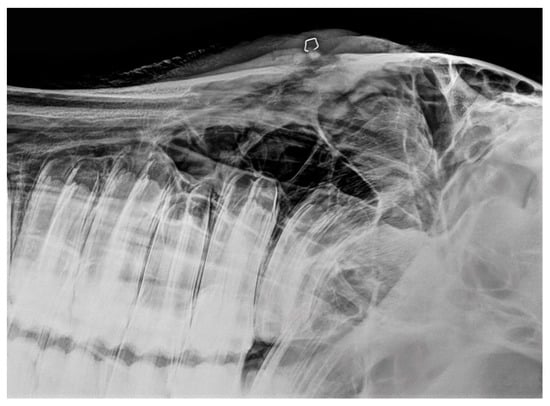

3.2. Imaging Findings